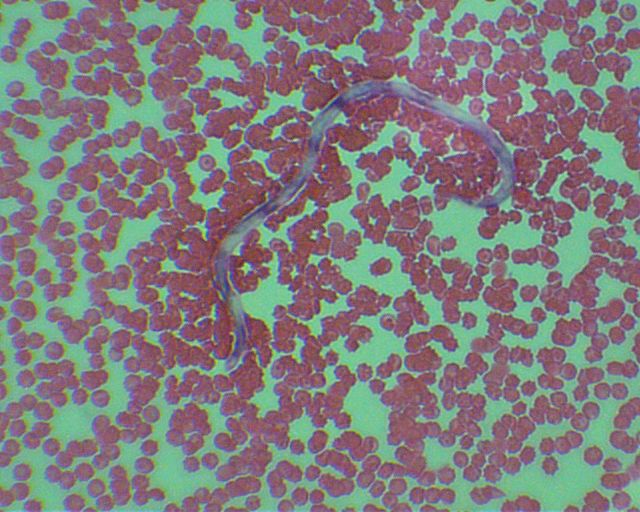

Профилактика дирофиляриоза у животных - фото презентация